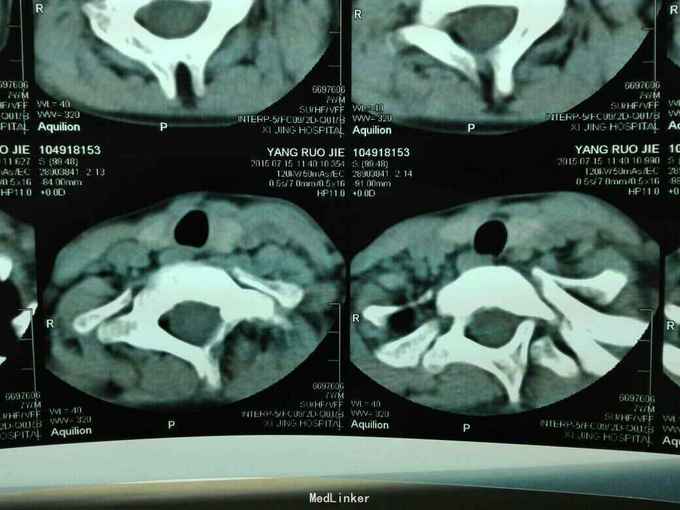

先天脊柱畸形

先天脊柱畸形8年。